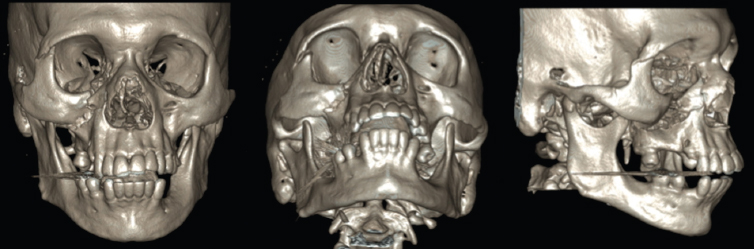

The zygoma is a spatially complex bone that articulates with the frontal bone, maxilla, temporal bone, and sphenoid. Zygomaticomaxillary complex (ZMC) fractures that occur with lower-velocity blunt impact often occur at these articulations. Spatially, they displace the ZMC with minimal comminution (Figure 15.2). Higher-velocity injuries (e.g., gunshot wounds) often cause comminution with more complex fracture patterns (Figure 15.3). By definition, given the anatomy of the zygoma, a ZMC fracture must affect the orbital floor or lateral orbital wall. Simultaneous reconstruction of the orbital floor is often indicated. ZMC fractures may cause deformity in facial width, orbital rim step-offs, cheek projection, and globe position. Medial displacement of the temporal process may cause trismus through impingement on the coronoid.